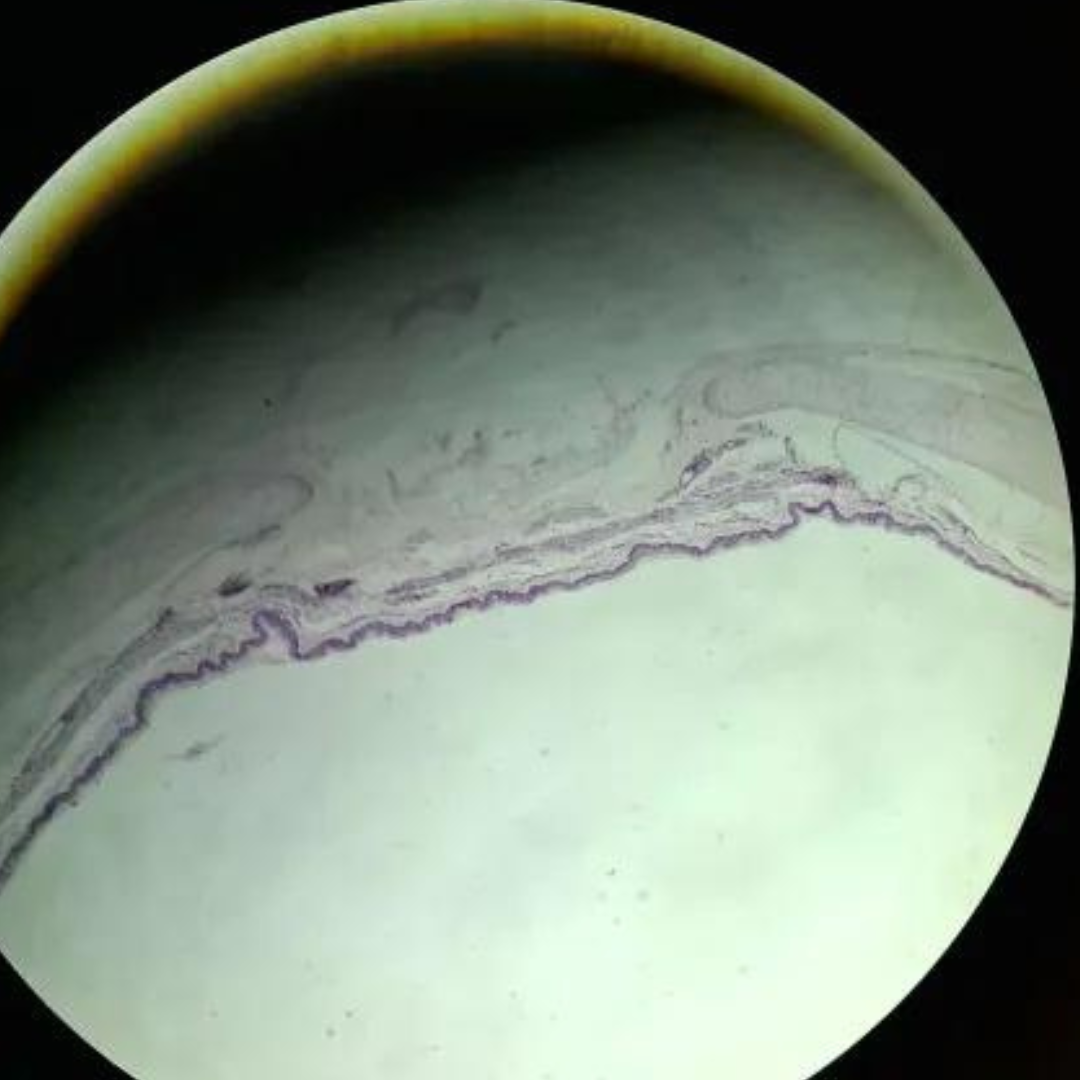

Bone

Bone

Bone

Bone

Bone